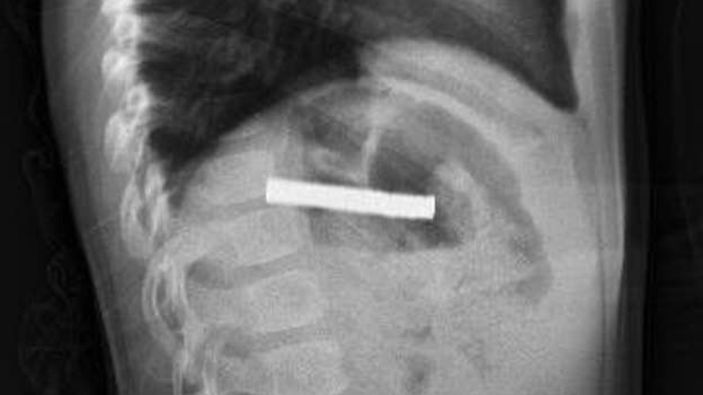

Fırat Üniversitesi Çocuk Gastroenteroloji Hepatoloji ve Beslenme Bilim Dalı Başkanı Prof. Dr. Yaşar Doğan, çocuk hastanın yemek borusuna yapışmış 19 mıknatısı endoskopik yöntemle çıkardı.

Mıknatıslar uzun süre yemek borusunda takılı kaldığı için yemek borusu ve mide girişinde zedelenmeler olurken, çocuğun sağlık durumunun iyi olduğu ve taburcu edildiği öğrenildi.